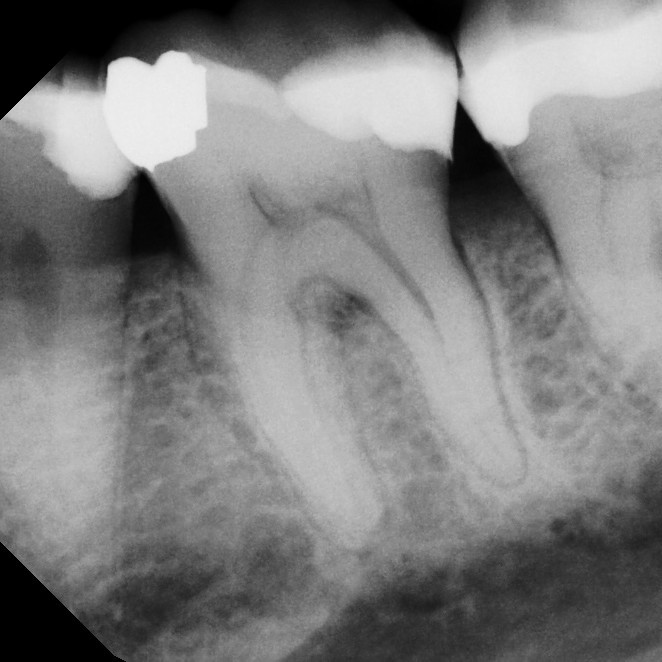

Root canal therapy is a specialized treatment designed to save a tooth that has been damaged by deep decay, trauma, or infection. Sometimes the problem causes noticeable pain or sensitivity, but in other cases it may develop quietly without obvious symptoms. During the procedure, the infected or damaged nerve tissue inside the tooth is carefully removed, the canals are disinfected, and the space is sealed to prevent further problems. Local anesthesia ensures you're completely comfortable throughout the process.

Thanks to advances in modern dentistry, root canals have become far more comfortable and efficient than they were in the past. Most patients report that the experience is comparable to having a standard filling, and recovery is typically quick. By treating the tooth promptly, you can avoid more serious dental issues, preserve your natural smile, and return to normal function without the need for extraction.